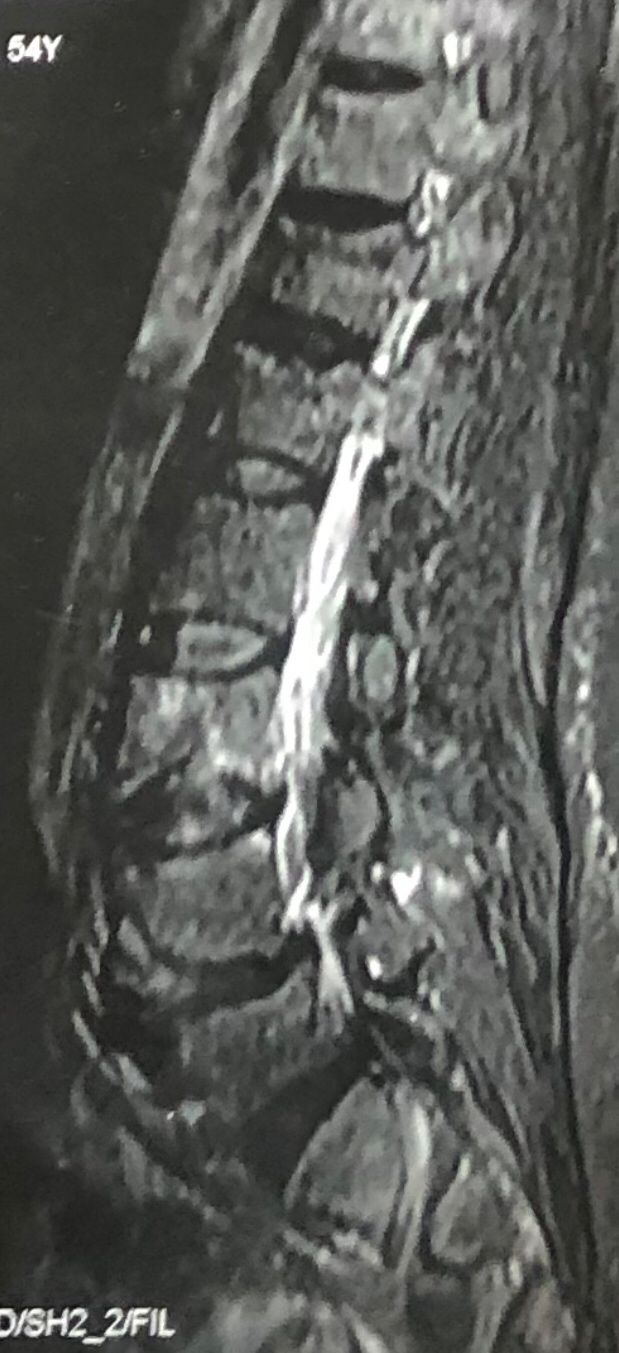

41 years old man presented to my clinic in October 2023 with acute and sever R neck pain with radicular pain to his R upper extremity along C6 dematom since 2 weeks ago. Examination didn’t show any upper motor signs. Was suggested urgent surgery

I ordered EMG/ NCV : showed mild R C6, C7 irritation without any active axonal loss

In his MRI was reported R. para R. IVF Massive extrusion. I decided to control his pain and manage this patient with reevaluation of patient every other session. For 5 sessions i just used acupuncture and laser and IFC and mild adjustments to his R. T3-T7 and mild arthosteem to above and below involved segment. Cervical adjustment considered contraindicated for this patient. From session 6th- 8th i started to use mild/gentle cervical decompression. He used soft cervical collar all the time. His pain decreased by 80 percent

I gave him cervical traction pump to be used 3-5 times per day at home for the next 3 months and i released the patient. He was evaluated every week once for one month and after that every 2 weeks. After 3 month I repeated MRI. Size of the herniated disc was reduced greater than 50 percent. Asked him to do another mri in 6 months

In general: Precise selection of the patients, examination,diagnosis, plan of management, reevaluation and treatment can be done by doctors of chiropractic for the patients with spinal disc herniation and stenosis Moreover giving reasonable time to these kind of patients under direct supervision by their chiropractic doctors can prevent unnecessary surgery. Proper selection of these kind of patients is another important fact that can be done precisely by chiropractors.

MRIs before and after proper management of this patient: